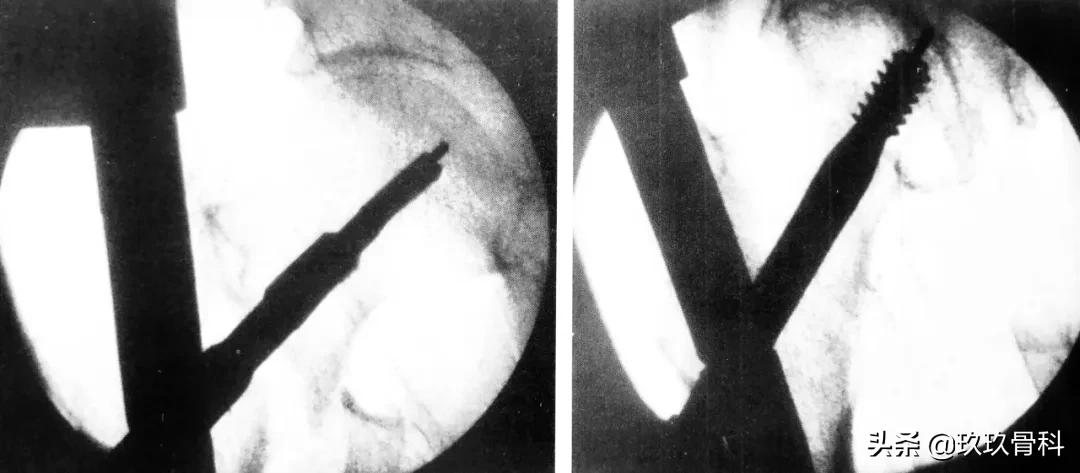

正位拉力钉导针位置、侧位拉力钉导针位置

骨科取髓内钉的视频,骨科髓内钉内固定术式简写

阶梯钻钻孔、正位拉力钉位置

侧位拉力钉位置、远端锁钉置入